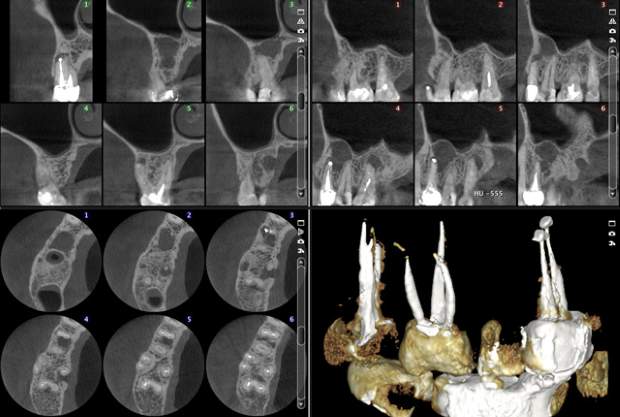

Planmeca ARA™ Artefact Removal Algorithm

Potilaan metallipaikat ja juuritäytteet saattavat aiheuttaa KKTT-kuviin varjoja ja muita artefaktoja. Älykäs Planmeca ARA™ -artefaktanpoistoalgoritmi poistaa nämä artefaktat tehokkaasti Planmeca ProMax® 3D -kuvista.

Without artefact removal

With Planmeca ARA artefact removal algotrithm

Planmeca ProMax 3D s Ø50x50 mm, vokselikoko 75µm

Planmeca ProMax 3D Mid Ø40x50 mm, vokselikoko 75µm